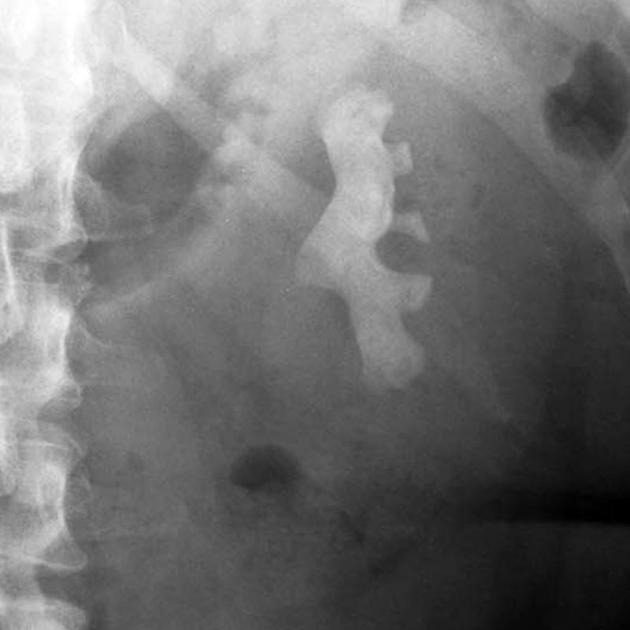

Sỏi thận hình san hô của nữ bệnh nhân

Bệnh nhân nữ 65 tuổi, từng được chẩn đoán sỏi san hô thận trái nhưng không đồng ý can thiệp do triệu chứng không đáng kể.

Sau một thời gian, bệnh nhân nhập viện trong tình trạng sốt cao, mệt nhiều. Kết quả thăm khám cho thấy thận trái đã bị ứ nước kèm nhiễm khuẩn do sỏi, đồng thời xuất hiện nhiễm khuẩn huyết từ đường tiết niệu.

Theo BS Phạm Đức Trọng, Đơn vị Tiết niệu - Bệnh viện An Bình, người bệnh được phẫu thuật cấp cứu dẫn lưu thận khẩn cấp để giải áp, giúp nước tiểu thoát ra ngoài, đồng thời kiểm soát tình trạng nhiễm trùng trước khi có thể tiến hành các bước xử lý sỏi triệt để. Việc trì hoãn can thiệp trước đó đã khiến bệnh lý tiến triển phức tạp hơn, làm tăng nguy cơ biến chứng và kéo dài quá trình điều trị.